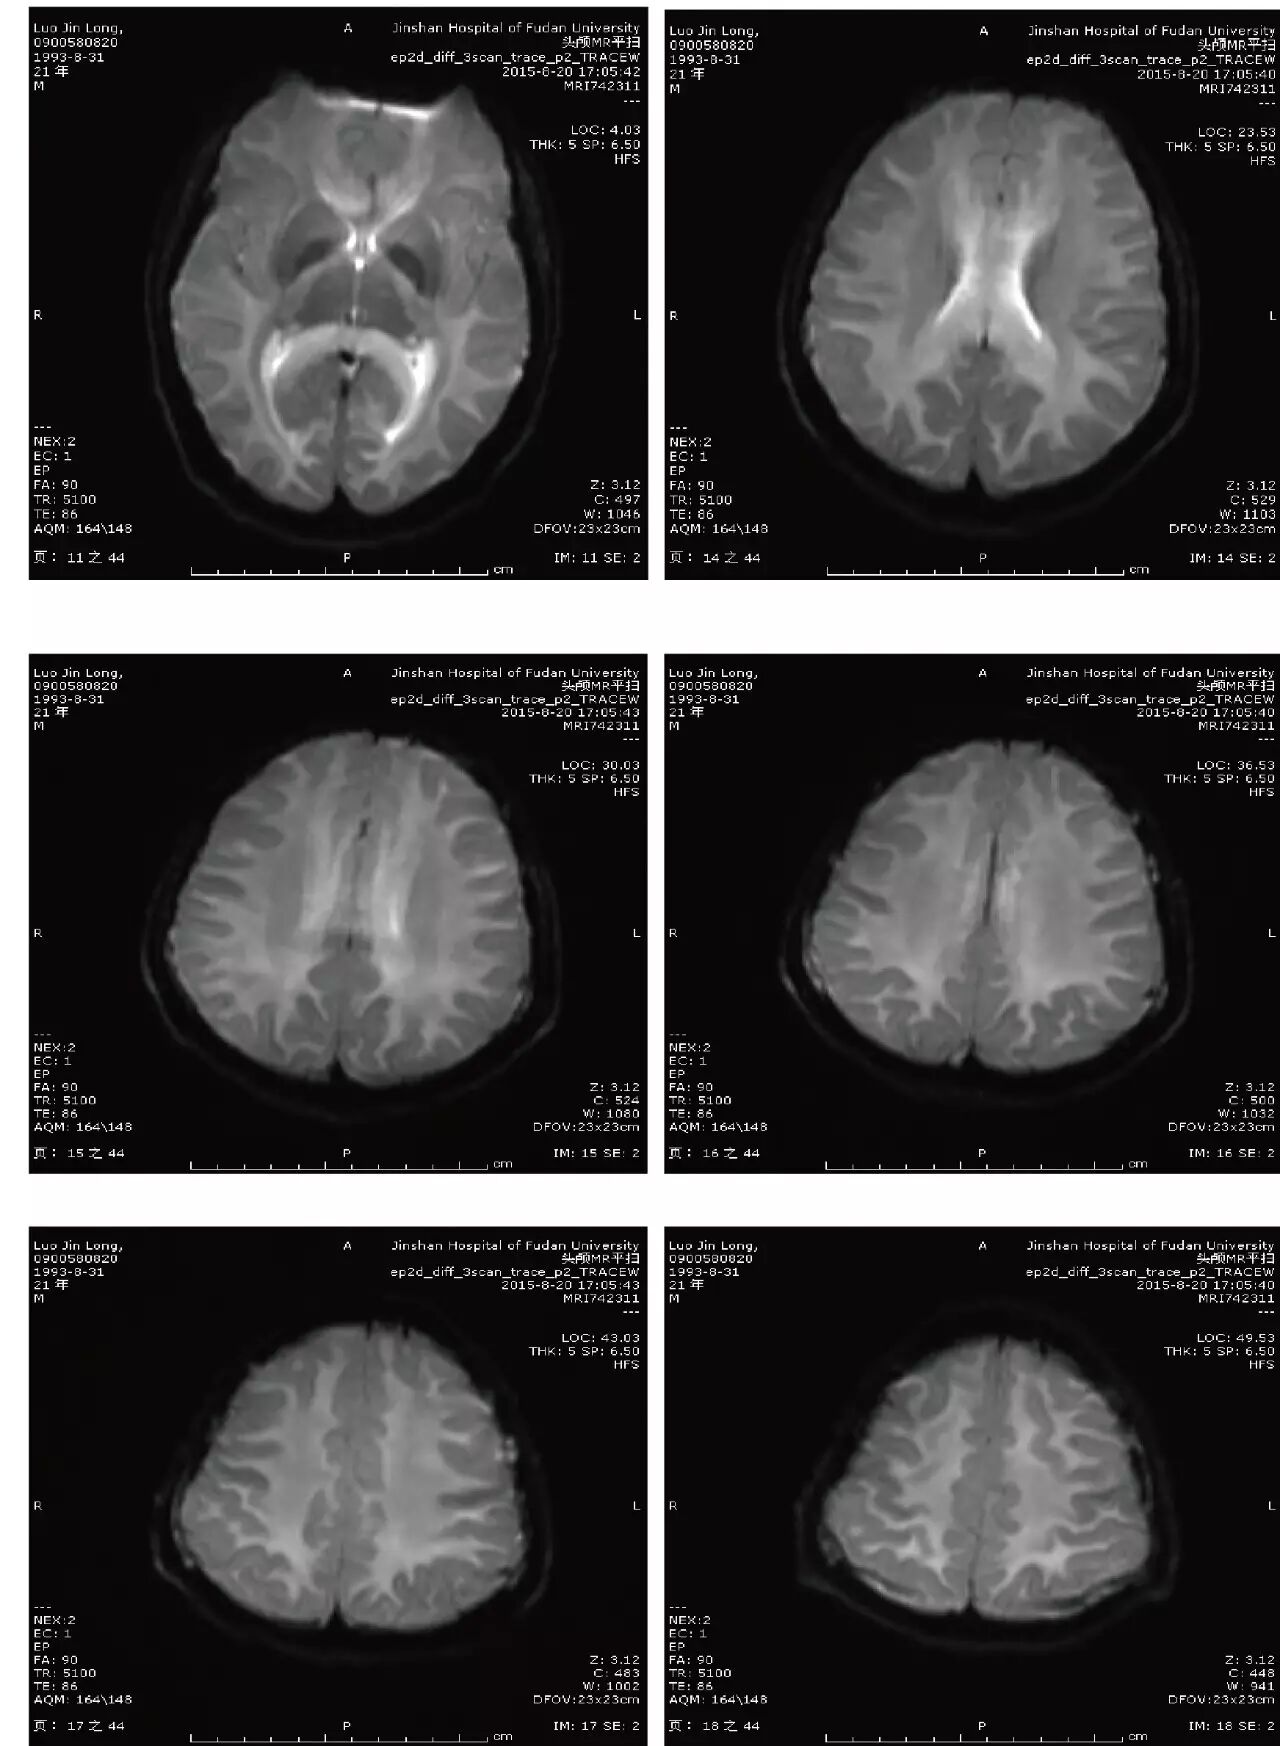

主诉:头痛、反应迟钝、口齿不清4天

现病史:头中线部位钝痛,反应迟钝,口齿不清,无发热,无恶心、呕吐,无饮水呛咳,四肢乏力。无麻木不适。2天后出现视物模糊。外院头颅CT:两侧大脑半球低密度灶。

(点击查看高清图)